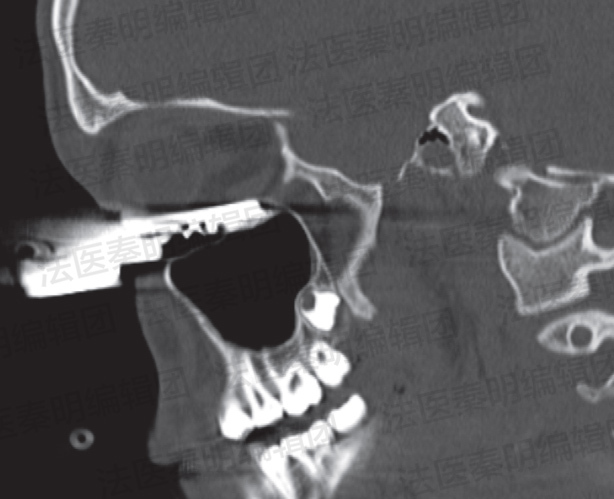

2008年6月,医生的急诊诊室来了一位左眼眶下部被钥匙刺入的患者。患者口述他是在踢足球的过程中发动头球时,他胸前佩戴的钥匙刚好飞到头与足球之间。于是,钥匙在头球作用力下刺入了他的眼眶。通过CT(计算机断层扫描)检查,医生发现钥匙深深地插入到了眼眶的组织中,但是庆幸的是,眼球并未受到损伤。于是,医生们对这位患者进行了手术,将钥匙取出。术后给予了患者抗生素治疗,用以预防感染。最终这位患者痊愈出院,并且没有留下视力方面的后遗症。然而,他佩戴钥匙一类项链饰品的行为,违反了足球协会关于踢足球时与安全相关的规定

钥匙刺入左侧眼眶 图片来源:参考文献[2]

CT扫描显示的钥匙与眼眶内组织损伤关系 图源:参考文献[2]